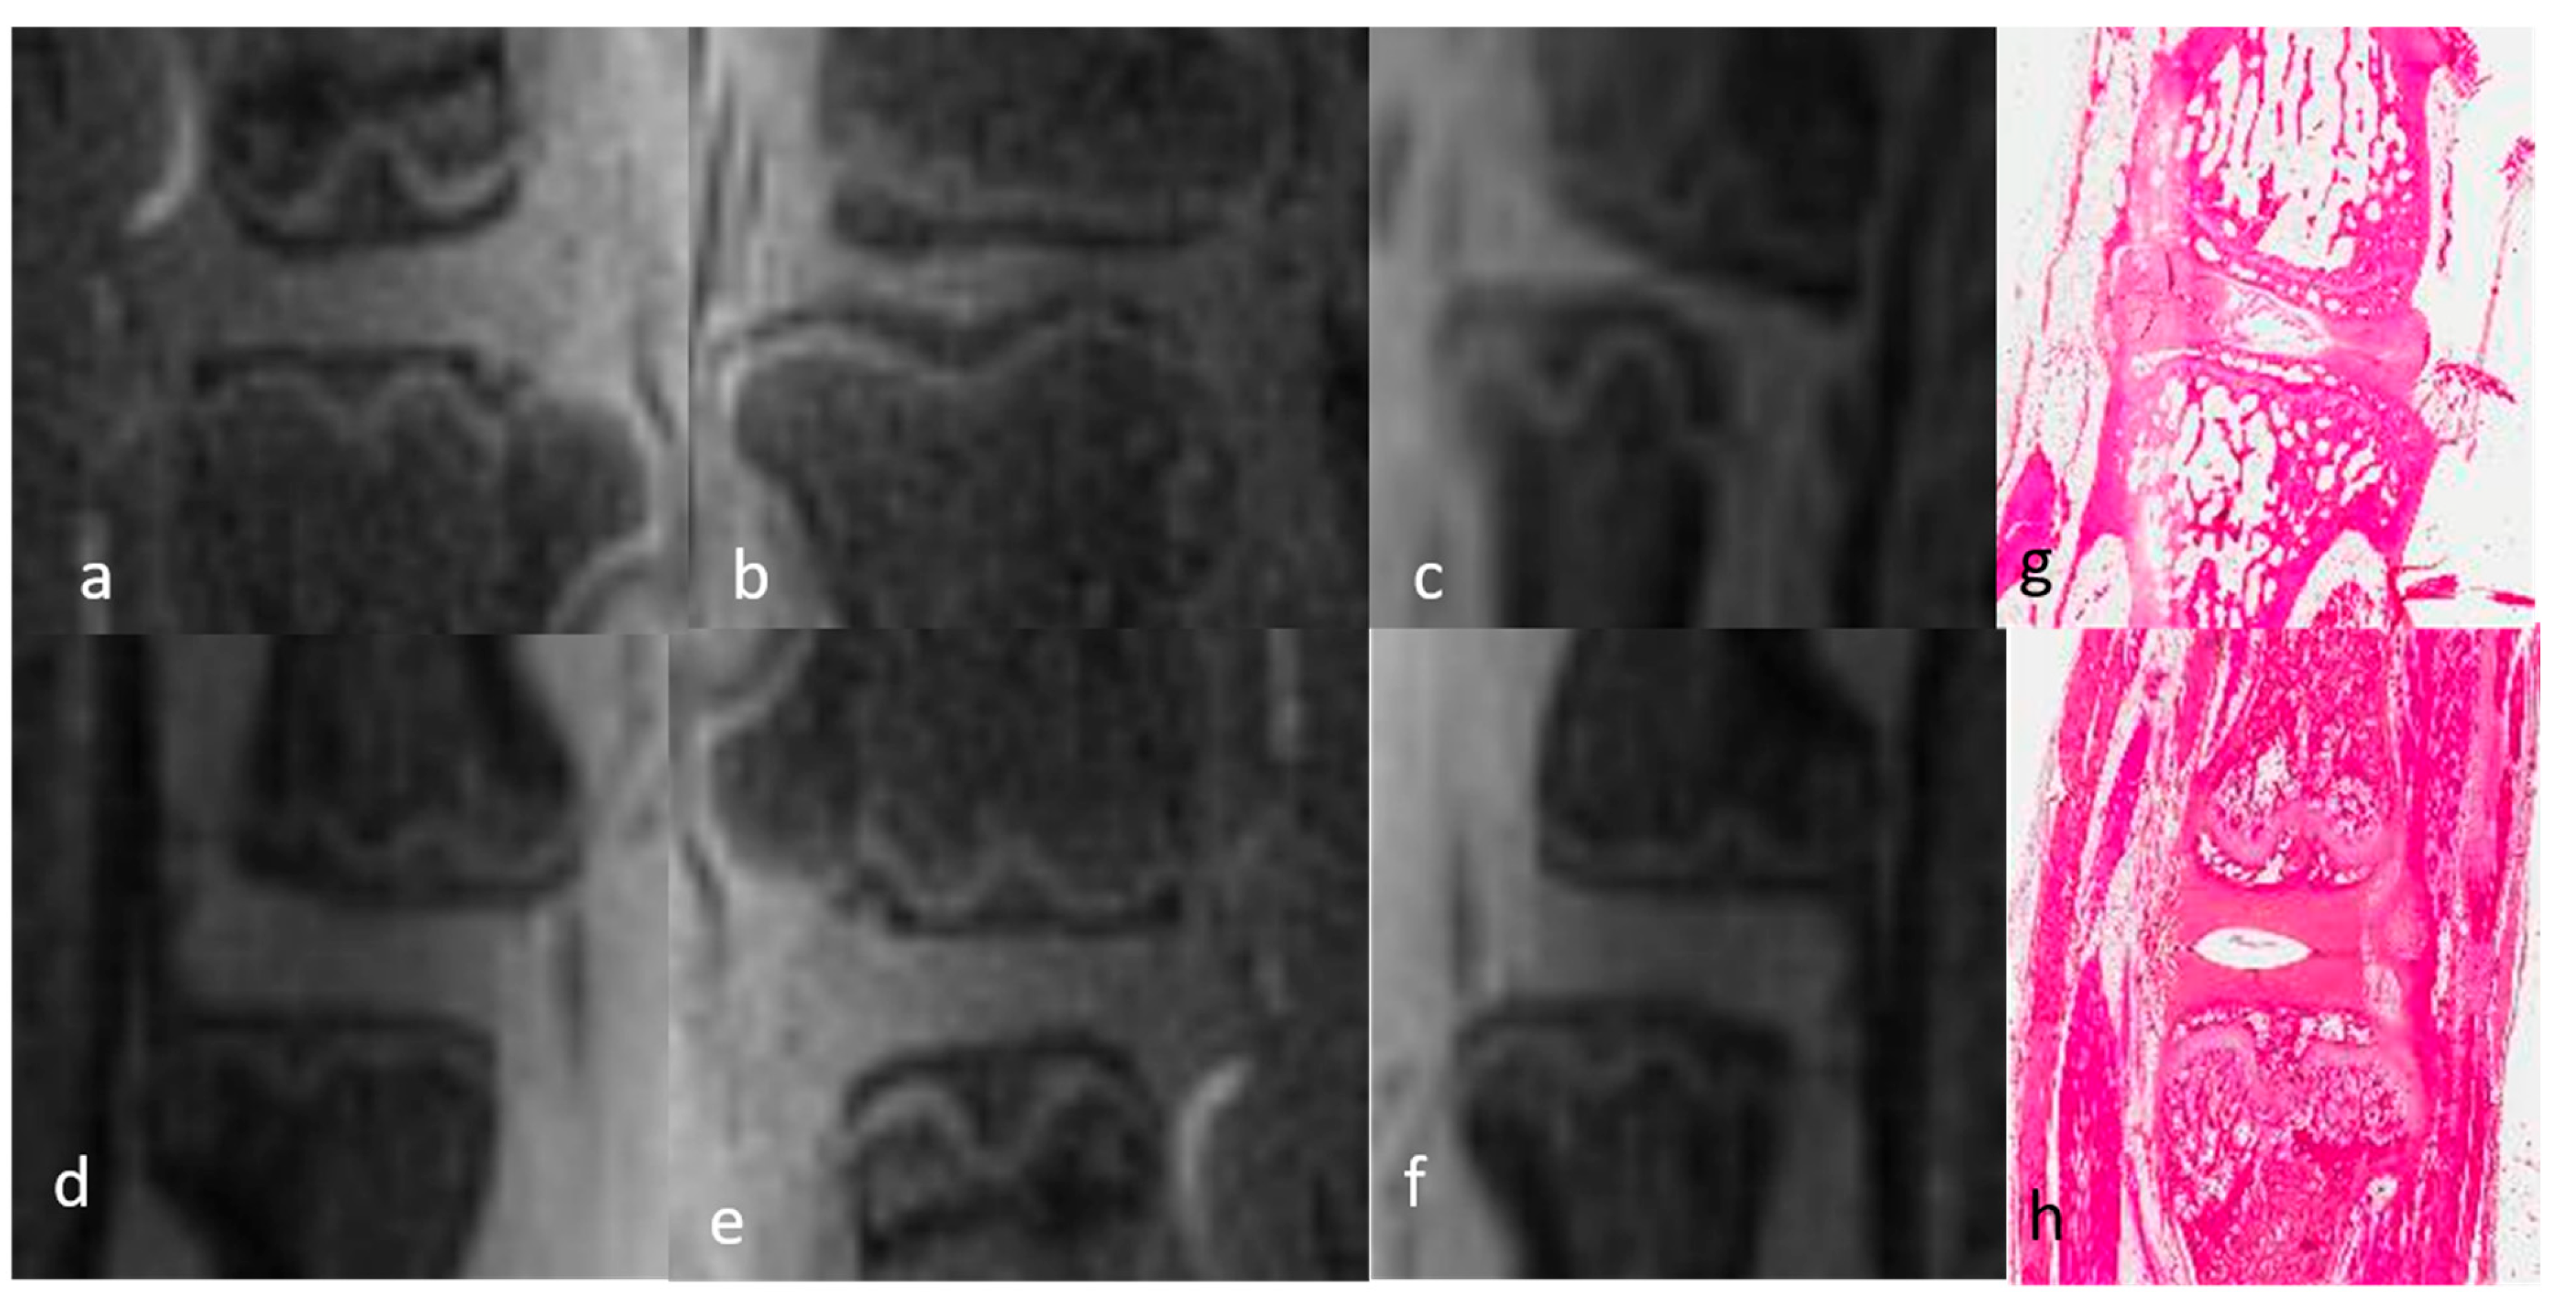

3.1.1. Qualitative Analysis of the Normal DVC (Table 1 and Table 2)

3.1.2. Qualitative Analysis of the DVC in DDD Rats (Table 3)

3.3. Histological Evaluation